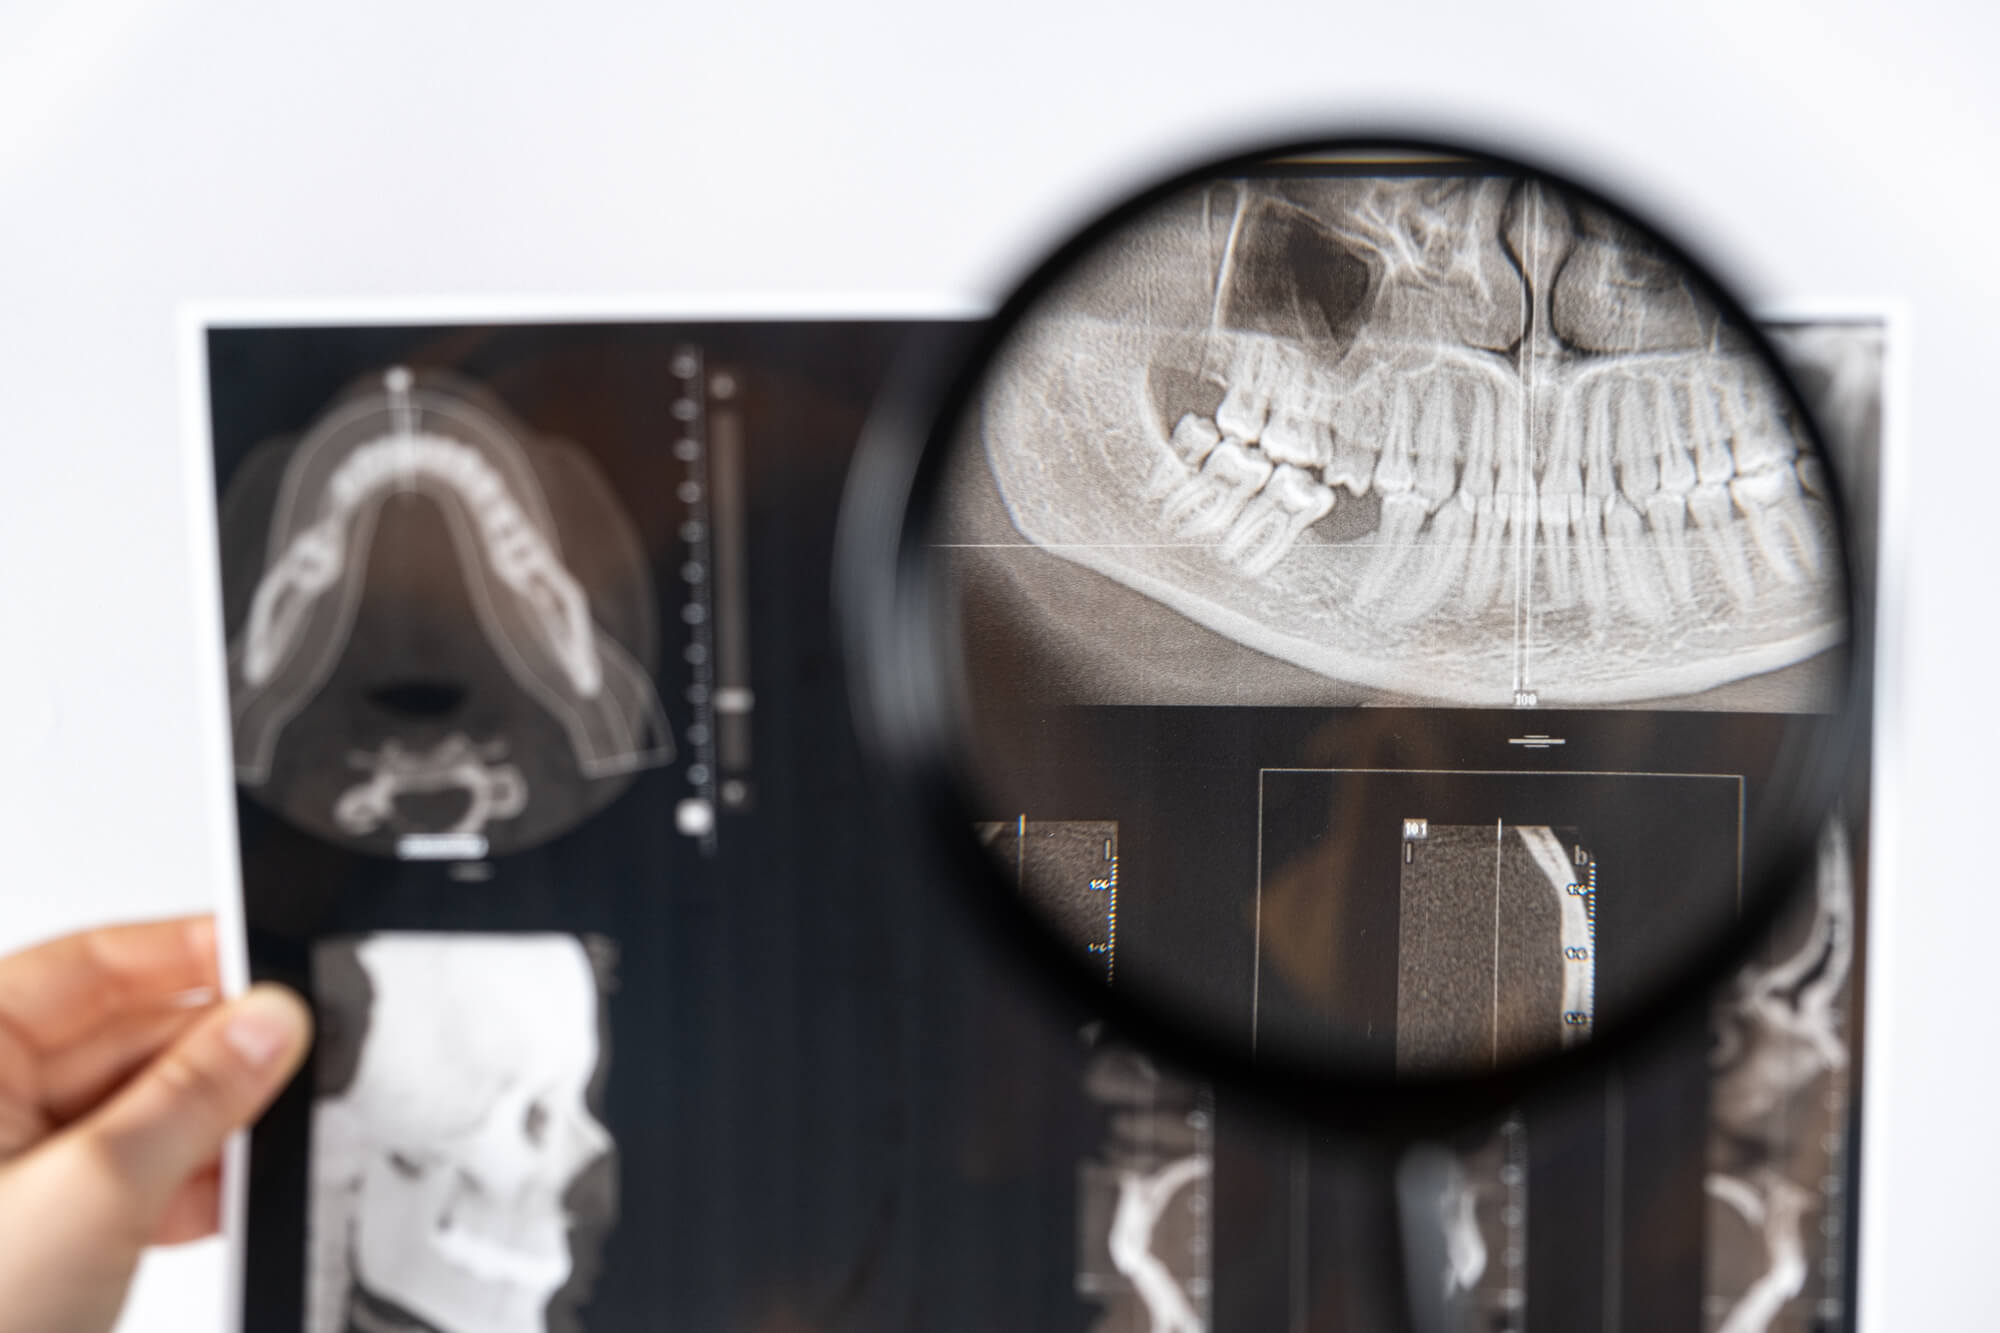

インプラント治療の前には診察や検査が重要です。レントゲンやCT撮影で歯や骨の状態を調べ、虫歯や歯周病の検査や全体の噛み合わせ、歯並びをチェックする必要があります。

インプラント治療には、患者様の口腔内を精密に診断するための最新の設備が欠かせません。特にCTは、顎の骨の構造や神経の位置を立体的に把握するために重要です。これにより、インプラントの埋入を行う際のリスクを最小限に抑えることができます。